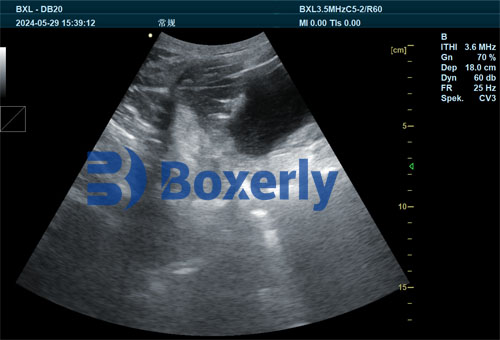

B-Mode Ultrasonography

B-mode ultrasound offers two-dimensional cross-sectional imaging of the ovary, revealing follicles as hypoechoic (dark) spherical structures. High-frequency probes (7.5–10 MHz) provide better resolution, enabling detection of follicles as small as 1–2 millimeters in diameter.

For quantifying follicular reserve, veterinarians count the antral follicle count (AFC) visible on ultrasound. The AFC is a reliable proxy for the total primordial follicle pool, validated by correlation studies with histology and hormonal markers like anti-Müllerian hormone (AMH).